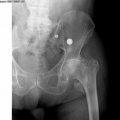

В приемное отделение Ожерельевской больницы Каширской ЦРБ обратился 39-летний мужчина, который жаловался на головную боль и боль в позвоночнике. Со слов пациента, травма произошла, когда он переходил мост, но поскользнулся, не удержал равновесие и упал с него. Как сообщили в ЦРБ, после осмотра врачом и рентгенографии, пациенту был поставлен диагноз перелом позвоночника и черепно-мозговая травма.

«В ходе проведенных обследований у пациента были выявлены переломы грудных позвонков и тяжелая черепно-мозговая травма. Особенности данной патологии в том, что существует определенный период, в течение которого человек нормально себя чувствует. Однако, это состояние обманчиво, и если вовремя не оказать помощь, могут возникнуть необратимые последствия, включая летальный исход» - рассказал врач-травматолог Игорь Шарашкин.